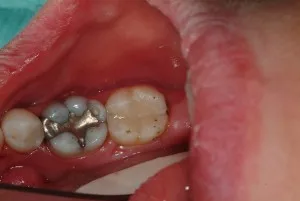

Teeth are isolated w/ a non latex barrier as part of our protocol to reduce or eliminate the exposure to mercury dust and vapors created in removal.

Once the amalgam is safely removed from the tooth, the underlying dark decay is evident. This is then removed and disinfected prior to restoration of the tooth.